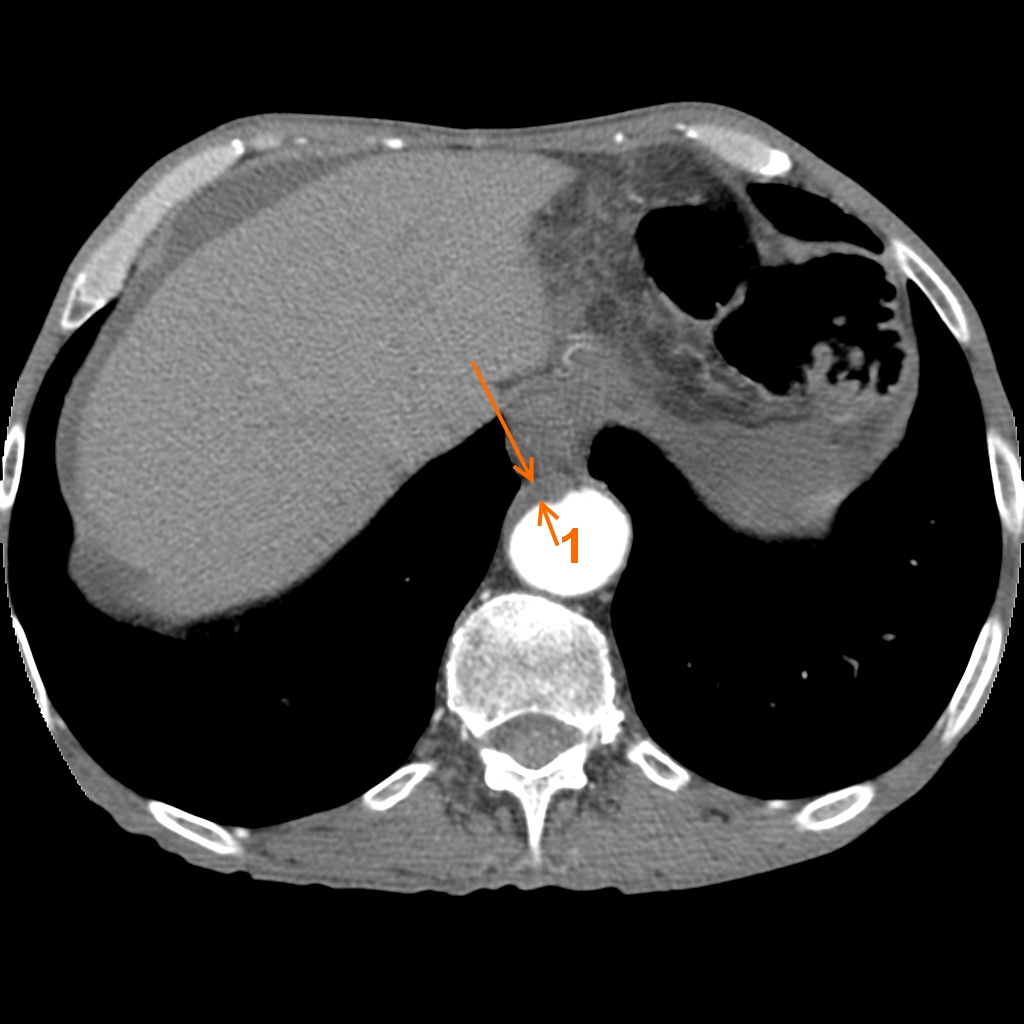

Фотографии и снимки КТ легких без контрастных веществ

Раздел: Визуальный дайджест